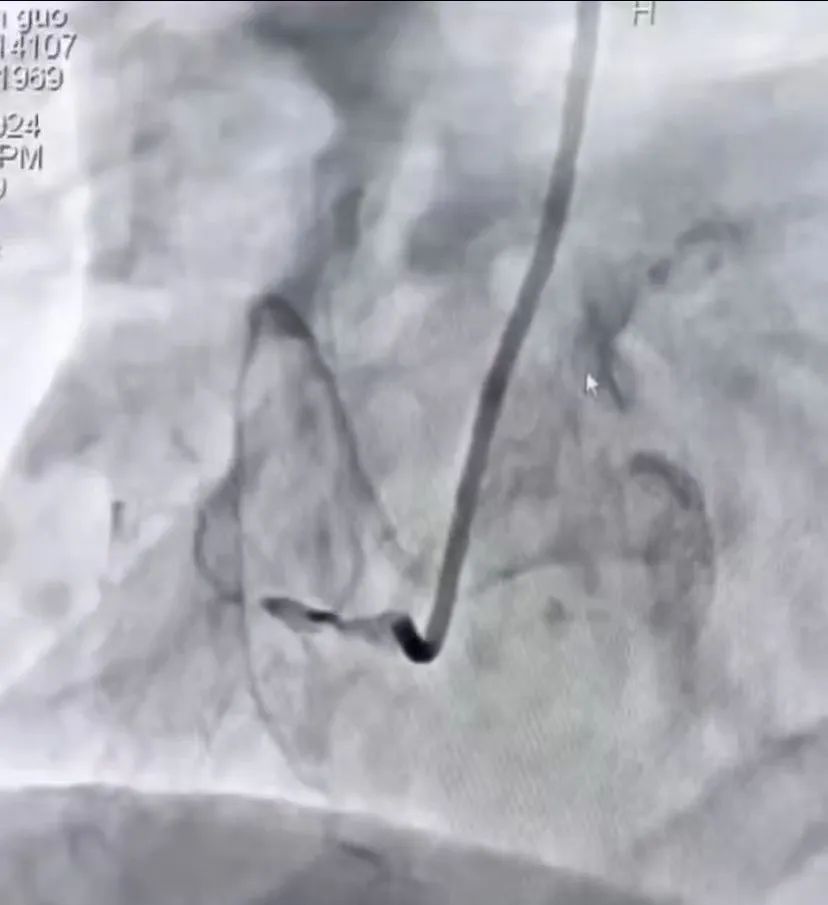

庆幸的是,送入导管室后,患者在经过IABP及药物治疗后可以于半卧位下耐受冠脉介入手术治疗,随后心内科介入团队迅速行冠脉造影,显示前降支急性闭塞、右冠脉慢性闭塞、回旋支中重度狭窄,在与死神百米赛跑的比赛中,团队先快速开通了前降支,解决了罪犯血管,随后又开通了右冠脉,过程中使用血栓抽吸、临时起搏、IVUS、药物球囊植入术等多项操作,于2小时后顺利返回CCU病房。